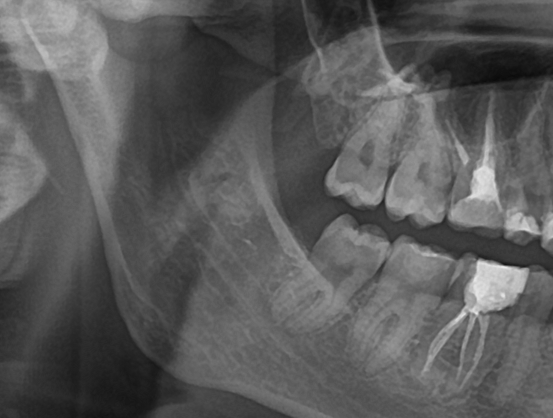

• расположены неправильно (фактически горизонтально), коронковая часть зубов мудрости упирается в соседние 7 зубы. Нужно удалять по тем же причинам, что и частично прорезавшиеся 8 зубы, когда они упираются в корни 7 зубов

Снимок взят с сайта shoes-web.ru Нижний зуб полностью находится в кости, шансов на его прорезывание 0, зато на разрушение 7 зуба и появление скученности зубов из-за него ближе к 100%